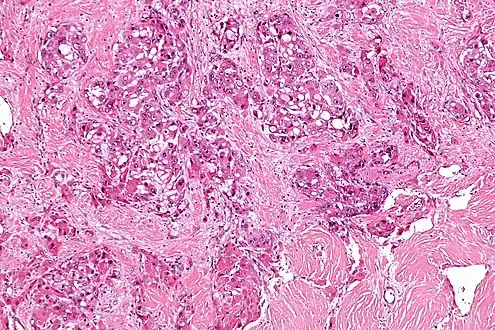

| Micrograph of fibrolamellar hepatocarcinoma showing the characteristic laminated fibrosis between the tumor cells with a low NC ratio. H&E stain. | |

The histopathology of FLC is characterized by laminated fibrous layers, interspersed between the tumor cells. Cytologically, the tumor cells have a low nuclear to cytoplasmic ratio with abundant eosinophilic cytoplasm.[1] Tumors are non-encapsulated, but well circumscribed, when compared to conventional HCC (which typically has an invasive border).

Intermed. mag.

Intermed. mag. High mag.